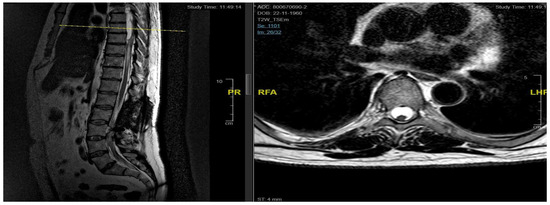

3.4.1. Case 1

| Patient | 1 | 2 | 3 | 4 | 5 |

|---|---|---|---|---|---|

| Age | 46 | 48 | 62 | 43 | 68 |

| Gender | M | M | M | F | F |

| Level | T12–L2 | C5–C6 | T7–T10 | T8–T9 | T8–T11 |

| Location | Intramedullary | Intradural | Intradural–Extradural | Intramedullary | Intradural |

| Primary/secondary | Secondary | Secondary | Secondary | Secondary | Secondary |

| Numbness | Yes | No | Yes | Yes | Yes |

| Gait disturbances/ataxia | No | Yes | No | Yes | Yes |

| Lumbar pain | No | No | Yes | Yes | No |

| Urinary–bowel dysfunction | Yes | No | Yes | No | No |

| Limb weakness | Yes | Yes | No | No | No |

| Paraplegia | No | No | Yes | No | No |

| Sexual disfunction | Yes | No | No | No | No |

| Surgical treatment | lysis of adherences and syrinx cavity opening | resection of the cystic formation and adhesiolysis | resection of the cystic formation and adhesiolysis | resection of the cystic formation and adhesiolysis | resection of the cystic formation and adhesiolysis |

| Complications | CSF fistula | infection | None | CSF fistula | None |

| KPS pre-op (%) | 70 | 50 | 70 | 80 | 90 |

| KPS post-op (%) | 80 | 50 | 60 | 90 | 80 |

| ASIA score pre-op | C | B | B | C | D |

| ASIA score post-op | D | B | C | C | D |

| Follow-up (years) | 2 | 2 | 2 | 3 | 1 |